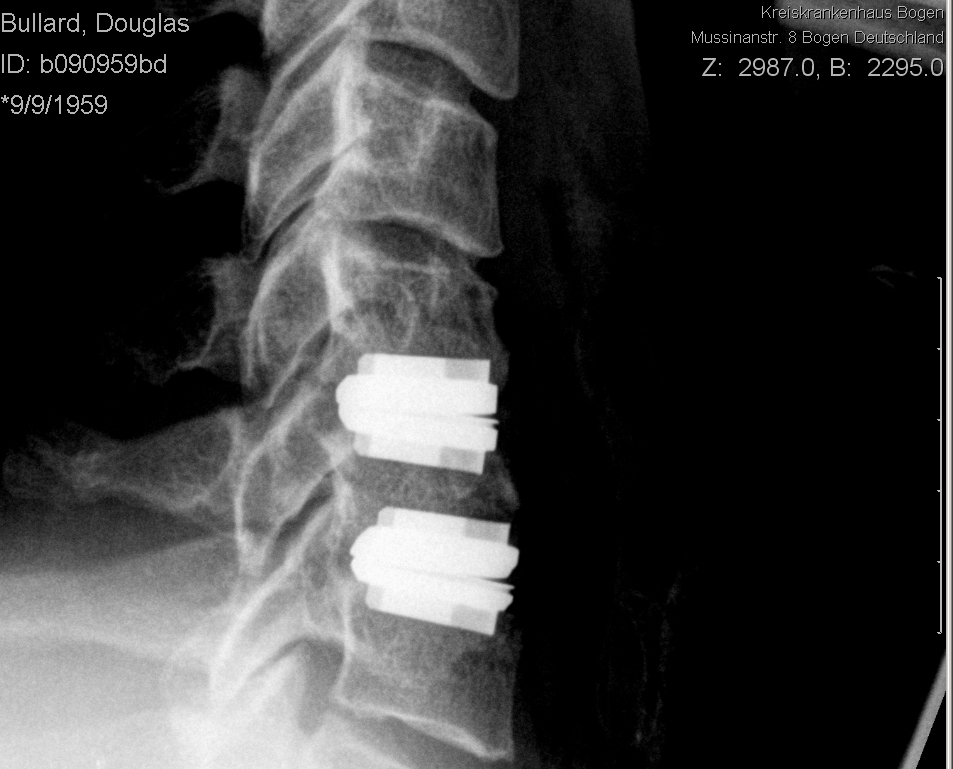

Post op side.jpg preview

The end result - artifical discs. The old discs have been removed, the offending bits of bone removed, and the new joints inserted.